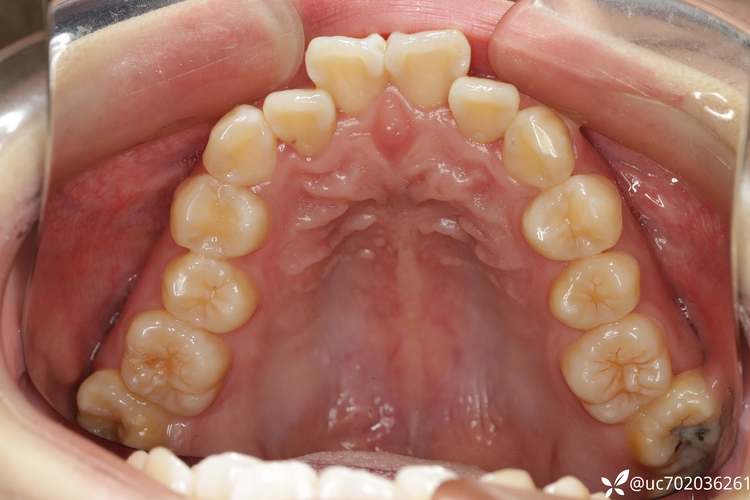

拔除“上4下5”后,正畸医生会通过固定矫治器(如金属托槽、陶瓷托槽)或隐形矫治器,施加持续、轻柔的生物力,引导牙齿按预设方向移动,具体移动机制包括:

- 前牙内收:上颌前牙(切牙、尖牙)在弓丝牵引下向舌侧移动,关闭拔牙间隙,改善前突;下颌前牙同步内收,协调上下唇关系。

- 后牙前移:上颌后牙(第一磨牙、第二前磨牙)向近中移动,与下颌磨牙建立中性咬合(上颌第一磨牙近中颊尖咬合于下颌第一磨牙颊沟);下颌后牙前移调整咬合接触点,分散咀嚼压力。